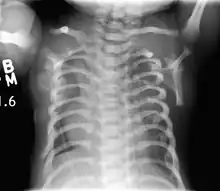

CXR of a newborn with asphyxiating thoracic dysplasia. Note the short ribs.

Lateral CXR of the same person above